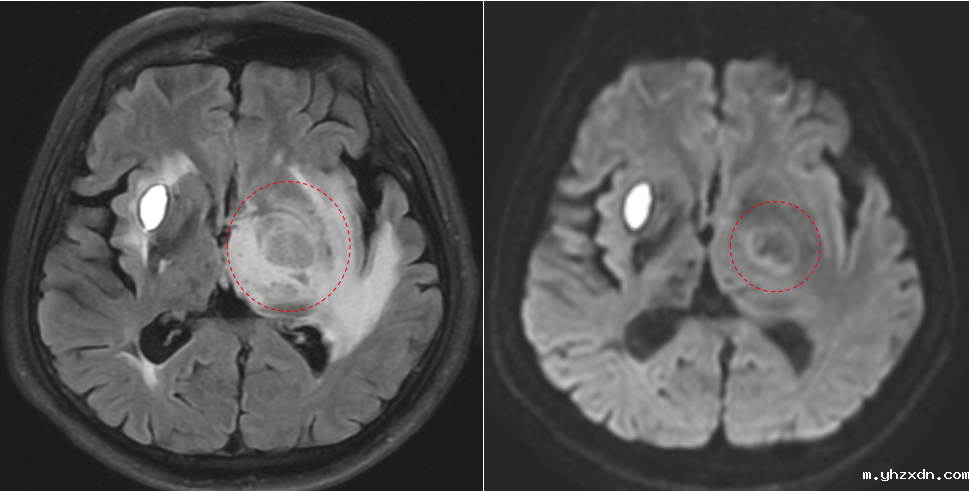

在问诊过程中,医生敏锐地察觉到L先生的症状可能与更严重的病有关。肢体活动障碍和认知功能障碍,往往是脑血管疾病、神经系统退行性疾病,甚至是肿瘤性病变的信号。为了尽快查明病因,医生与家属沟通后,决定为李L先生增加MRI头颅平扫。

快速确诊:肺癌脑转移的真相